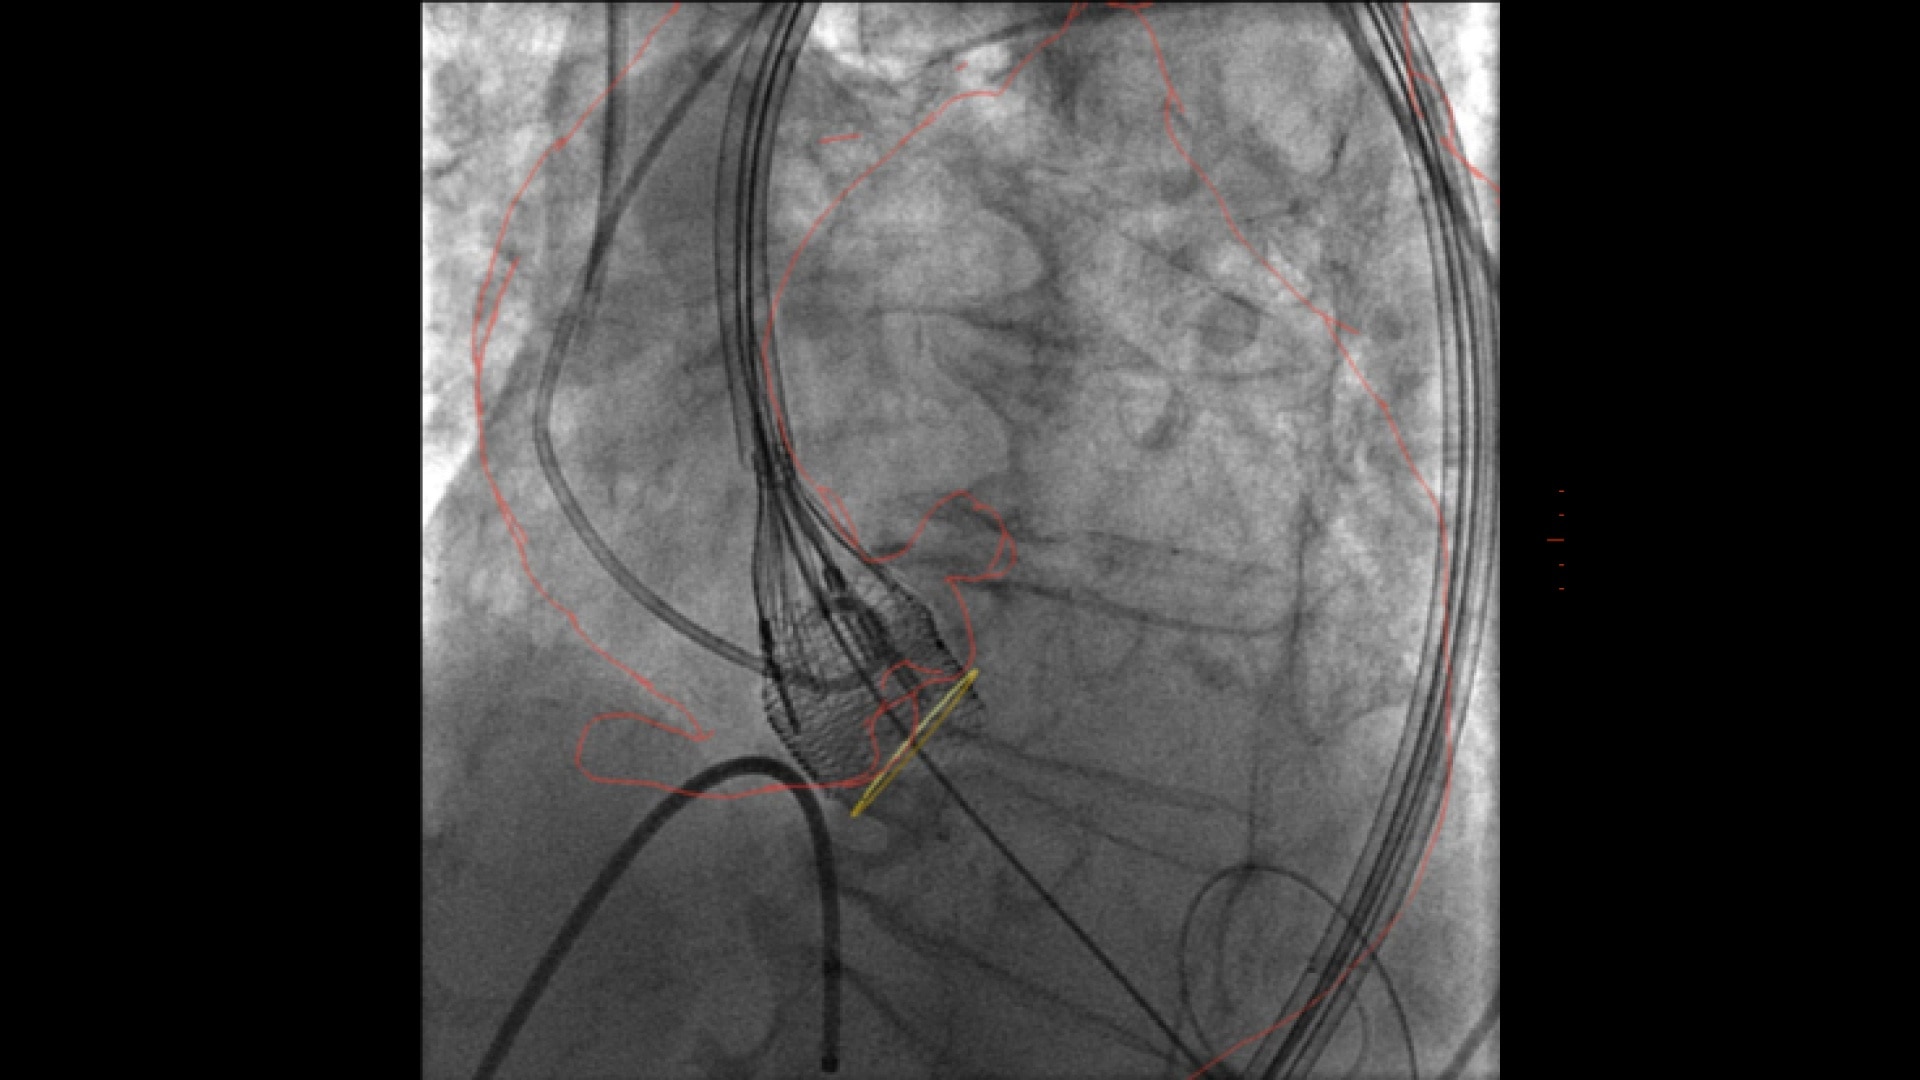

Left Atrial Appendage Closure

Augmented guidance for more confidence with LAAC

GUIDE

3D fusion helps guide each step with confidence, from the trans-septal puncture to the device deployment. Significantly reduce procedure time, while decreasing contrast media & dose.

ASSESS

Once the device is deployed, employ echocardiography to confirm the device location and evaluate compression before releasing the device⁴.